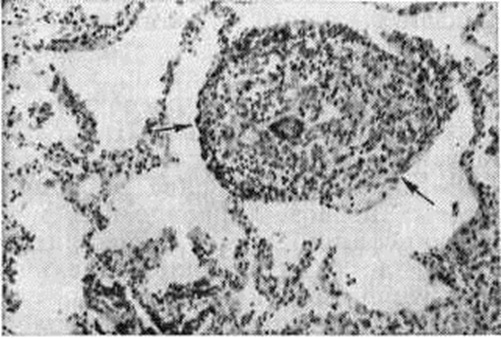

Однако все факты, приводившиеся в разное время в доказательство туберкулёзной природы Саркоидоз, оказались несостоятельными. Не подтвердились сообщения о якобы высокой частоте контактов больных Саркоидоз с бациллоносителями туберкулёза, сочетании Саркоидоз и туберкулёза у одного и того же больного, обнаружении возбудителей туберкулёза в органах, поражённых Саркоидоз Представлению о туберкулёзной природе Саркоидоз противоречат и другие данные. Так, в отличие от туберкулёза, Саркоидоз редко наблюдается у детей, сравнительно редко поражает серозные оболочки и, по-видимому, никогда не поражает надпочечники; кроме того, на фоне отчётливого снижения заболеваемости туберкулёзом в экономически развитых странах уменьшения заболеваемости Саркоидоз не отмечается. Малоубедительны и ссылки на сходство гистологический строения гранулемы при этих заболеваниях, поскольку аналогичная морфологический картина обнаруживается и при других нозологических формах, например, бериллиозе. Важно и то обстоятельство, что при Саркоидоз оказались неэффективными самые мощные противотуберкулёзные средства при несомненной эффективности глюкокортикоидных гормонов. Некоторые исследователи считают Саркоидоз болезнью изменённой реактивности, то есть полиэтиологическим заболеванием, в основе которого лежит особая, возможно генетически детерминированная, реакция на самые различные факторы: бытовые, профессиональные и так далее, что не получило ещё, однако, убедительных доказательств. Не подтвердилось и предполагавшееся значение воздействия сосновой пыльцы, атипичных микобактерий, грибков. Обсуждается вирусное происхождение Саркоидоз, однако предполагаемый вирус не идентифицирован. Патогенез Саркоидоз также не ясен. Представляется несомненным значение изменённой иммунологический реактивности и прежде всего резкого снижения реакций гиперчувствительности замедленного типа, что, в частности, подтверждается анергией больных Саркоидоз к туберкулину. С помощью иммуноморфологические исследования клеток саркоидозной гранулемы выявлено наличие на их поверхности фиксированных иммуноглобулинов (смотри полный свод знаний) и комплемента (смотри полный свод знаний), рассматриваемых как клеточные фиксированные антитела. При электронно-микроскопическом исследовании клеток саркоидозной гранулемы обнаружены выраженные признаки белкового синтеза и активация секреторной функции эпителиоидных клеток, что также свидетельствует об образовании антител. При электронной микроскопии эпителиоидных клеток установлена их способность к коллагенообразованию и возможность трансформации в фибробласты. Данные о непосредственном повреждающем действии клеток саркоидозной гранулемы на окружающую ткань подтверждают участие в патогенезе Саркоидоз иммунных факторов. Патологическая анатомия. Патоморфологически Саркоидоз проявляется образованием эпителиоидно-клеточных саркоидозных гранулем, развитие которых сопровождается дистрофическими и некротическими изменениями окружающих тканей и процессами рубцевания. Саркоидозная гранулема (смотри полный свод знаний) имеет своеобразное строение. В её центре (рисунок 1) располагаются эпителиоидные клетки (смотри полный свод знаний), гигантские клетки (смотри полный свод знаний), макрофаги (смотри полный свод знаний). Иногда между ними выявляется небольшое количество гомогенных эозинофильных масс. Нередко в центре саркоидозной гранулемы формируются капилляры, эндотелиальные клетки которых являются, по-видимому, источником образования эпителиоидных клеток. Гигантские клетки бывают двух типов: с центральным (типа клеток инородных тел) и периферическим (типа клеток Лангханса) расположением ядер. В цитоплазме некоторых гигантских клеток можно обнаружить астероидные или сферические тельца — включения Шауманна. Периферическая часть гранулем образована лимфоидными клетками и фибробластами, количественные соотношения между которыми бывают различными. Нередко между клетками периферической части гранулемы видны коллагеновые волокна, разделяющие клеточные элементы и подчёркивающие слоистость строения гранулемы. Можно выделить два типа гранулем. Первый тип — так называемый штампованные, или склерозирующиеся, гранулемы (рисунок 2) — небольшие гранулемы, чётко отграниченные от окружающих тканей; по их периферии выражена фибробластическая реакция и признаки коллагенообразования. Второй тип — гранулемы больших размеров, нередко без чётких границ за счёт распространяющейся по соединительной ткани лимфоидно-клеточной инфильтрации; по периферии этих гранулем преобладают круглоклеточные элементы. Саркоидозная гранулема по своему строению сходна с гранулемами при туберкулёзе, бериллиозе, а также при ряде других заболеваний (смотри полный свод знаний: Гранулематозы), при которых может развиться саркоидоподобная реакция. Отличить саркоидозную гранулему от туберкулёзной не всегда просто. Основными дифференциально диагностическими морфологический признаками являются отсутствие в саркоидозной гранулеме казеозного некроза и бактерий и наличие капилляров. Ряд особенностей саркоидозной гранулемы, выявляемых с помощью гистохимических методов исследования (значительное содержание в клетках РНК и отсутствие кислых гликозаминогликанов), имеет для дифференциальной диагностики меньшее значение.